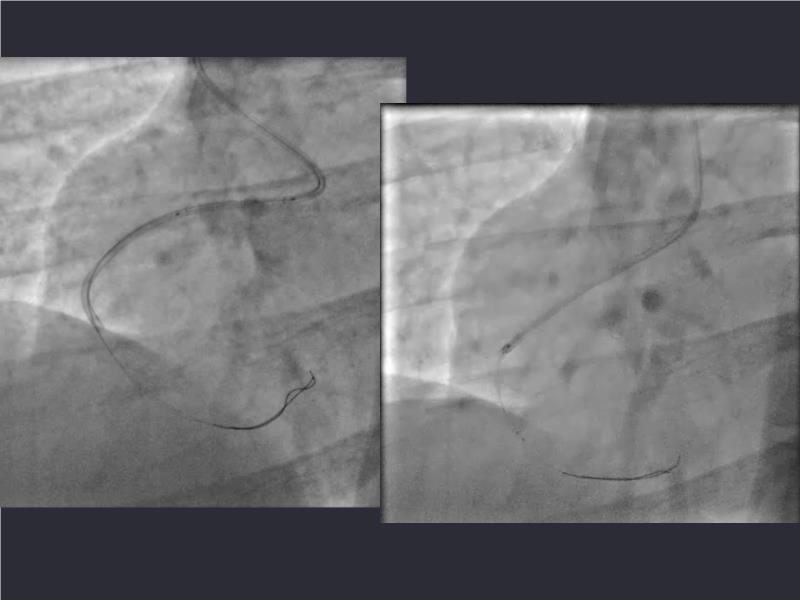

- To understand novel tools and techniques for effective management of bifurcation lesions and long diffused lesions using dedicated stenting solutions